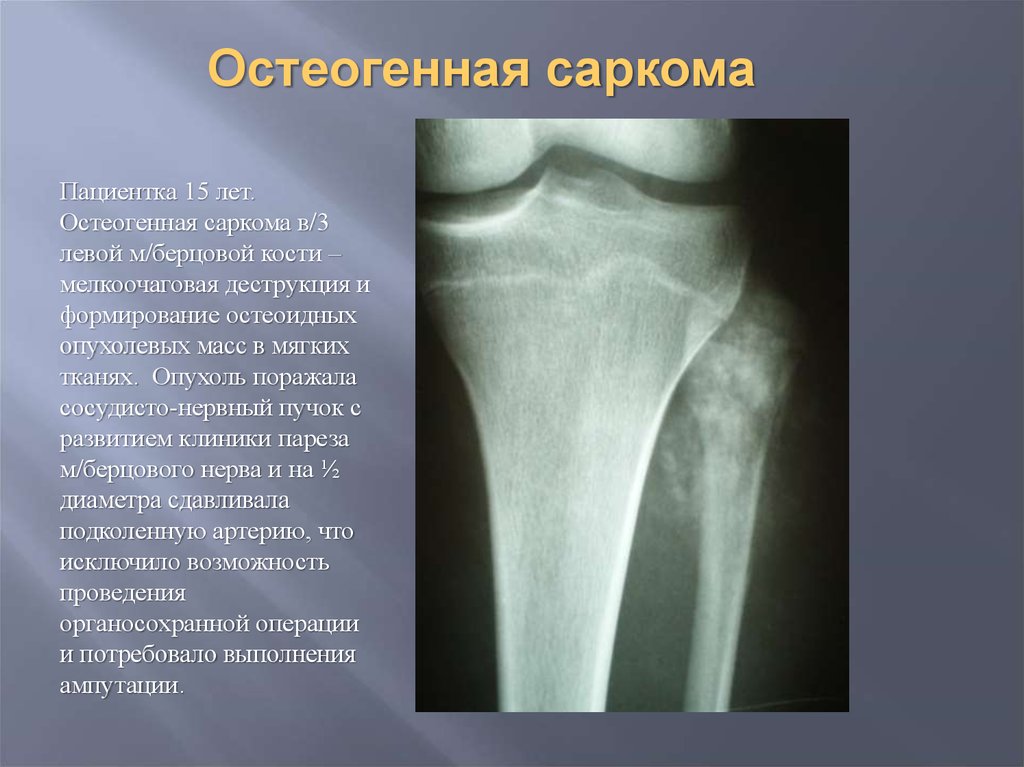

Рентгенологическая картина остеогенной саркомы кости - 98 фото